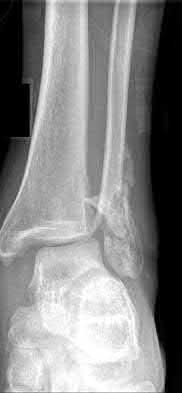

2. # A 35-year-old woman is involved in a head-on collision while driving. Initial radiographs are shown in Figures 8a and 8b. Injury to what vessel increases the risk for osteonecrosis of the injured bone?

5. Artery of the tarsal sinus Corrent answer: 4

The patient has a Hawkins type III talar neck fracture-dislocation with a risk of osteonecrosis ranging from 69% to 100%. Anatomic studies have shown that the artery of the tarsal canal supplies the lateral two thirds of the talar body.

The other vessels listed provide no significant contribution to the talus.